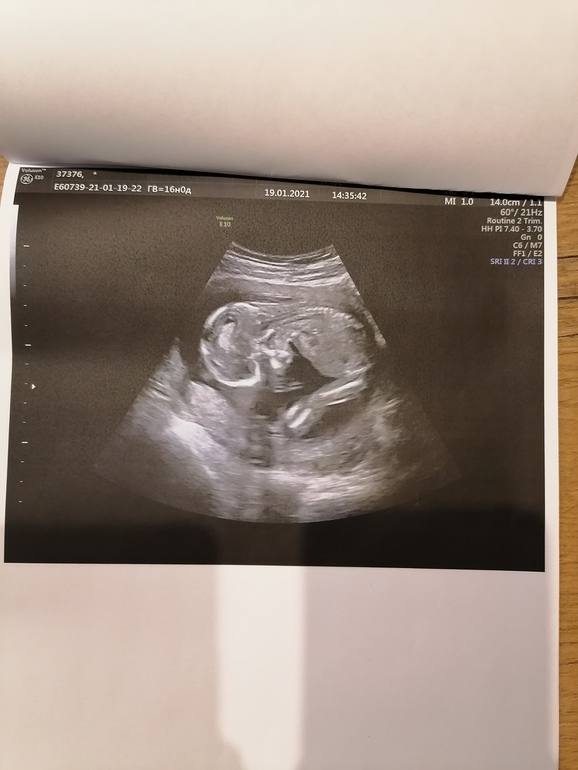

16 недель, фотки, узи у эксперта Пятых Н. С. 🙏🙏🙏👶💙💙💙

Я так счастлива, что с сыночком все хорошо👶🙏🙏🙏. Сидит на попе, прыгает, толкается, ручками машет🥰👶💙💙💙🙏🙏🙏. Шейка моя начала вести себя не айс, опять буду одевать пессарий.

По размерам опережает на неделю🥰

Ну и мой любимый сыночек, предположительно Константин Сергеевич👶💙💙💙🙏🙏🙏

Личико не показывает никак🙈👶